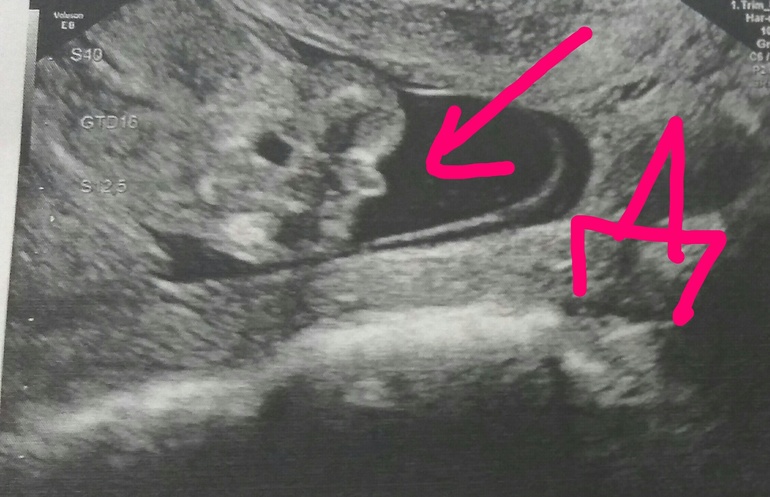

Пол на 14 неделе беременности по узи

Пол на 14 неделе беременности по узи 88 фото